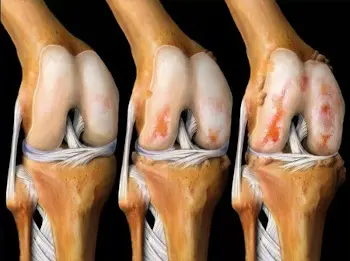

হাঁটুর জয়েন্টের তরুণাস্থি টিস্যুতে আর্থ্রোসিসের প্রভাব।

এই ছবিগুলো দেখো। সঠিক ছবিতে, জয়েন্টের জায়গা নেই, হাড়গুলো একে অপরের সাথে ঘষছে, যার ফলে তীব্র ব্যথা হচ্ছে। আর এই প্রক্রিয়া বন্ধ করা খুব কঠিন! কয়েক বছরের মধ্যে, ব্যক্তিটি অক্ষম হয়ে যাবে এবং নিজের যত্ন নিতে পারবে না।

এই সবই তরুণাস্থি টিস্যুকে নরম করে, জীর্ণ করে এবং পাতলা করে। প্রতিটি নতুন নড়াচড়ার সাথে, তরুণাস্থি জীর্ণ হয়ে যায় এবং বিকৃত হয়ে যায়, হাড়গুলি একে অপরের সাথে ঘষতে শুরু করে, যার ফলে অসহনীয় ব্যথা হয়।